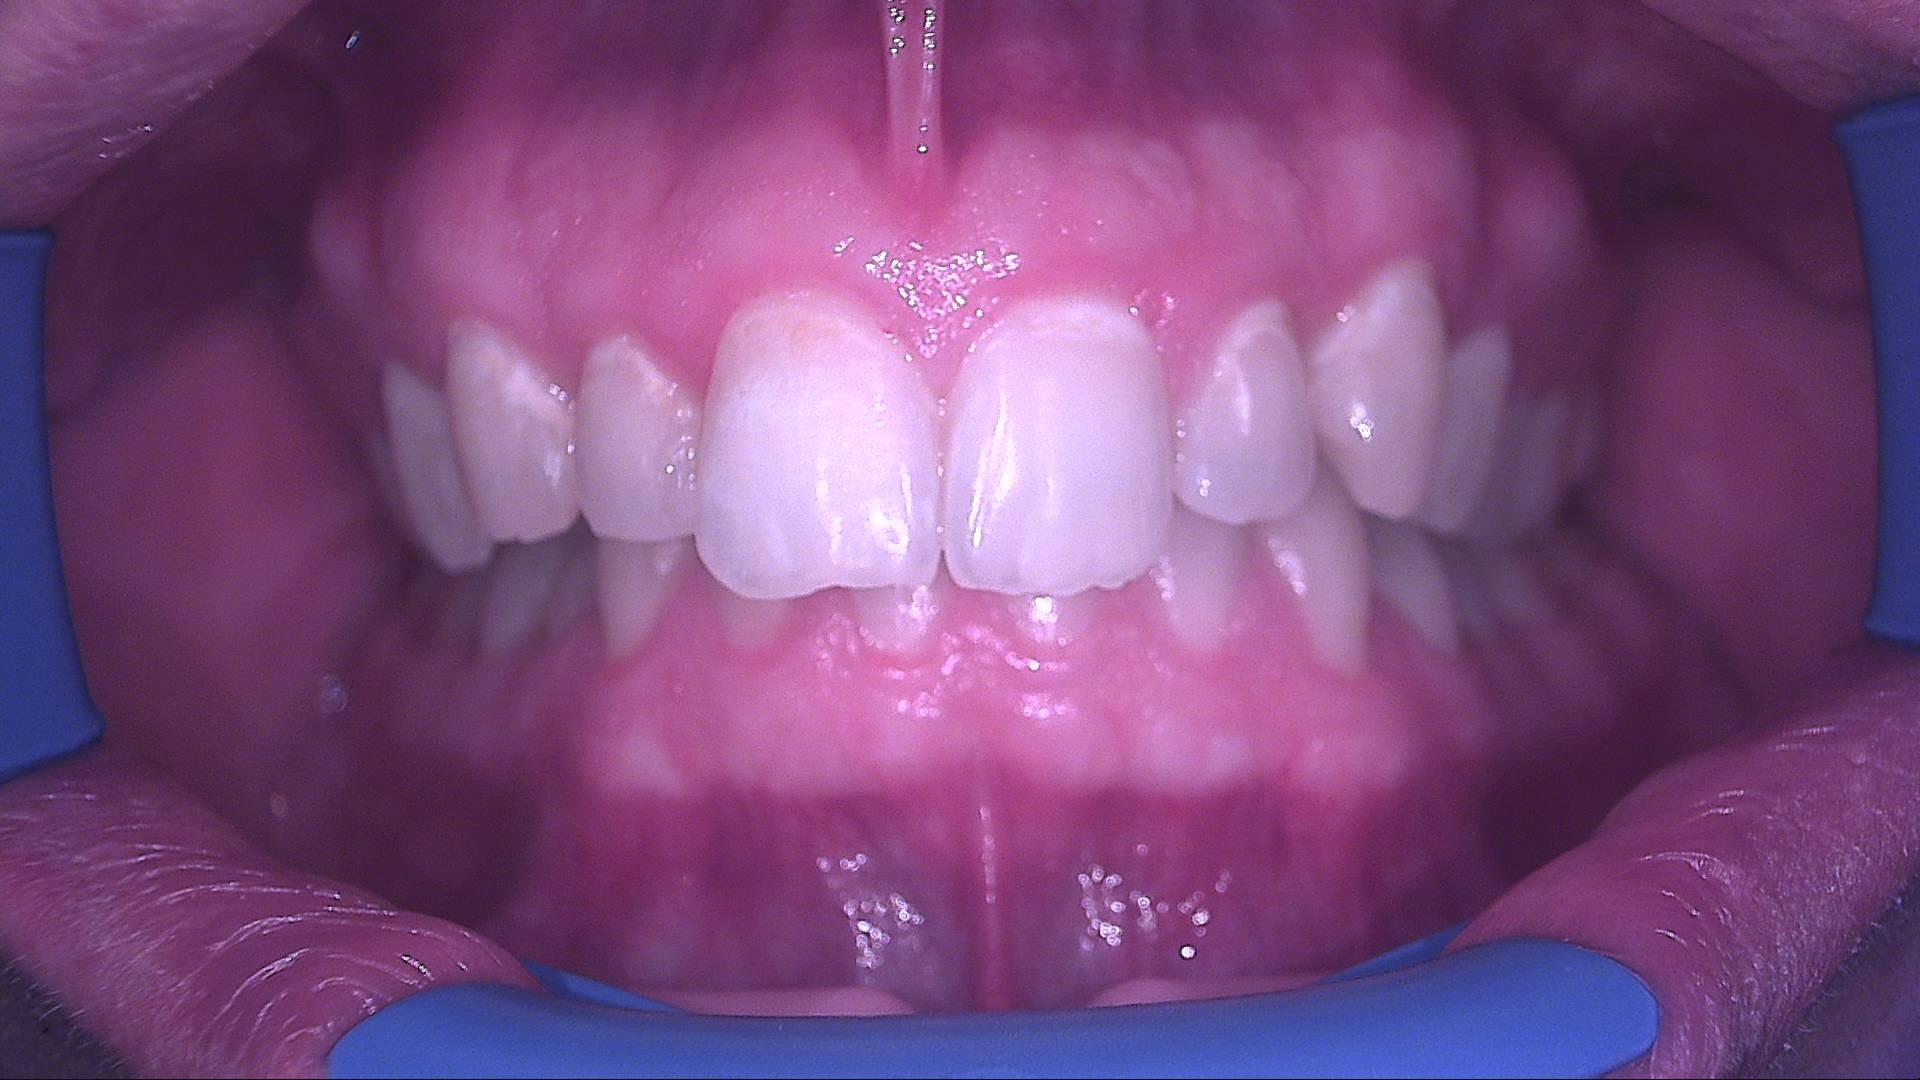

Paziente maschio, 25 anni, militare, riferisce fastidio estetico causato dalla presenza di aree bianche opache persistenti sugli incisivi superiori. All’esame

obiettivo in luce bianca si osservano white spot a livello degli elementi 11, 12, 21 e 22. L’esame in fluorescenza con QrayCam Pro conferma la presenza di zone a ridotta mineralizzazione con perdita di fluorescenza compresa tra –47,8% e –56,1% e area di white spot fino a 4007 px².

Fig. 1A - Situazione iniziale in luce bianca: aree bianche opache su 11, 12, 21 e 22.